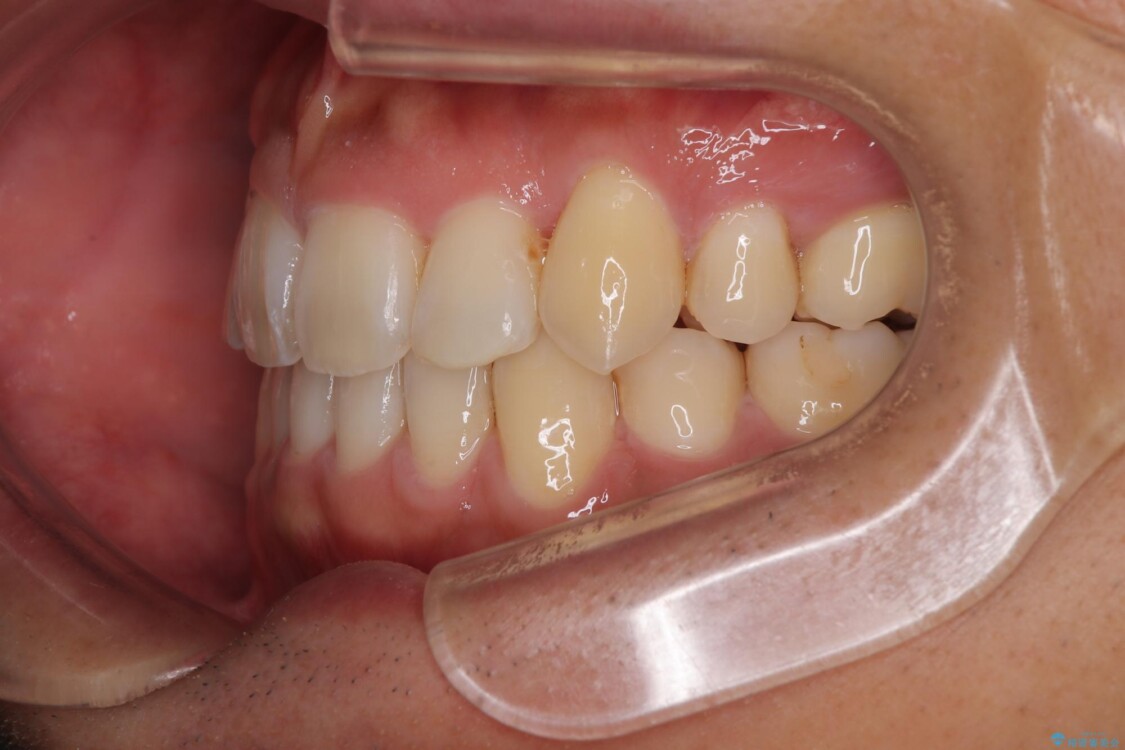

八重歯はきれいに整い、前歯もバランスよく収まり、横顔のラインも自然に改善されました。

治療後、患者様は「思い切り笑えるようになった」と大変喜んでくださいました。

治療後

• 八重歯と前歯のガタガタを抜歯矯正で治療|クリアブラケット使用例 治療後画像